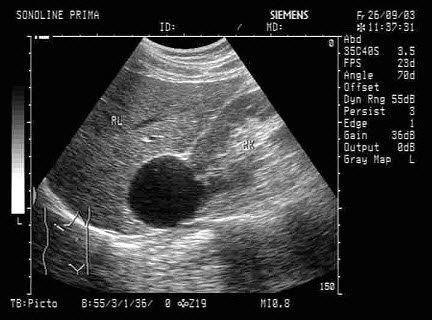

男性,右侧阴囊空虚,左侧可触及,于腹腔见一个椭圆形低回声光团,边界清晰,回声尚均匀,CDFI:血流信号丰富。如图所示,考虑为()

A.隐睾并精原细胞瘤

B.腹腔囊肿

C.腹腔淋巴结

D.畸胎瘤

E.腹腔淋巴瘤